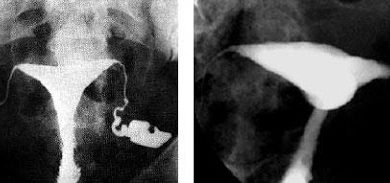

HSG, rahim ve tüplerin radyo-opak madde (boyalı madde) kullanılarak görüntülendiği bir radyolojik yöntemdir. Kadın-Doğum hekiminin radyoloji ünitelerinde uygulamasını yaptığı bu…

Bu muayene çoğu zaman, rahmin (uterus) ve fallop tüplerinin daha yakından incelenmesi amacıyla yapılır. Histerosalpingografi, rahmin (histero) ve fallop tüplerinin…

Rahim ağzından bir alet yardımıyla rahim içine ilaç verilip tüplerin ve rahim içinin araştırıldığı bir yöntemdir. Histerosalphingografide özel bir sıvı…

Rahim Filmi HSG nedir? Rahim filmi, rahim boşluğu, tüpler ve karın boşluğunun alt bölümünü incelemek için çekilen özel bir röntgen…